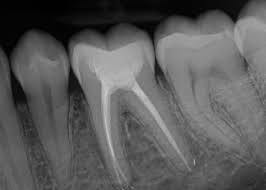

Endodoncija je postupak uklanjanja infekcije i oštećenog tkiva iz kanala korena, čime se čuva prirodan zub i sprečava dalje oštećenje. Tretman je precizan, bezbolan i efikasan, a za najbolje rezultate koristimo moderne tehnologije i savremene metode lečenja.

Omogućava preciznu dijagnostiku kanala korena. Brzo se prikazuje, pomaže u planiranju tretmana i povećava sigurnost i uspeh lečenja.